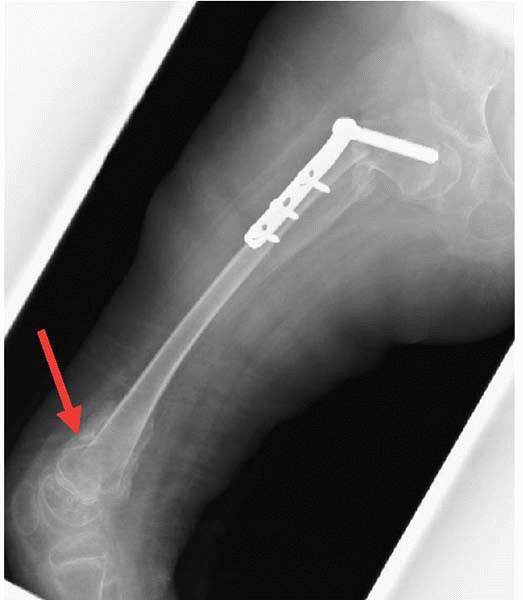

As mentioned previously, casts in children with CP cause lots of

problems. They are frequently used by some surgeons after hip

reconstructions hoping to lessen the pain for the first few

postoperative days. However, children maintained for a few weeks in a

spica cast after hip surgery are

a set up for skin pressure ulcers and distal femoral insufficiency fractures (Fig. 14-6).

The classic time for these fractures is a couple of weeks after the

casts come off when the physical therapy is aggressively trying to

regain knee motion. Periodic radiographs are recommended for several

![]() |

|

▪ FIGURE 14-6 A classic distal femoral insufficiency fracture with classic circumstances (arrow).

After hip reconstruction, the surgeon placed the child in a spica cast for a few weeks. Immobilization made the low bone density even worse. Of course, when cast came off, she was stiffer than ever, so she went to PT, where they enthusiastically went to work hard on her limited knee motion. Crack. Pain. Now what—more casting? |